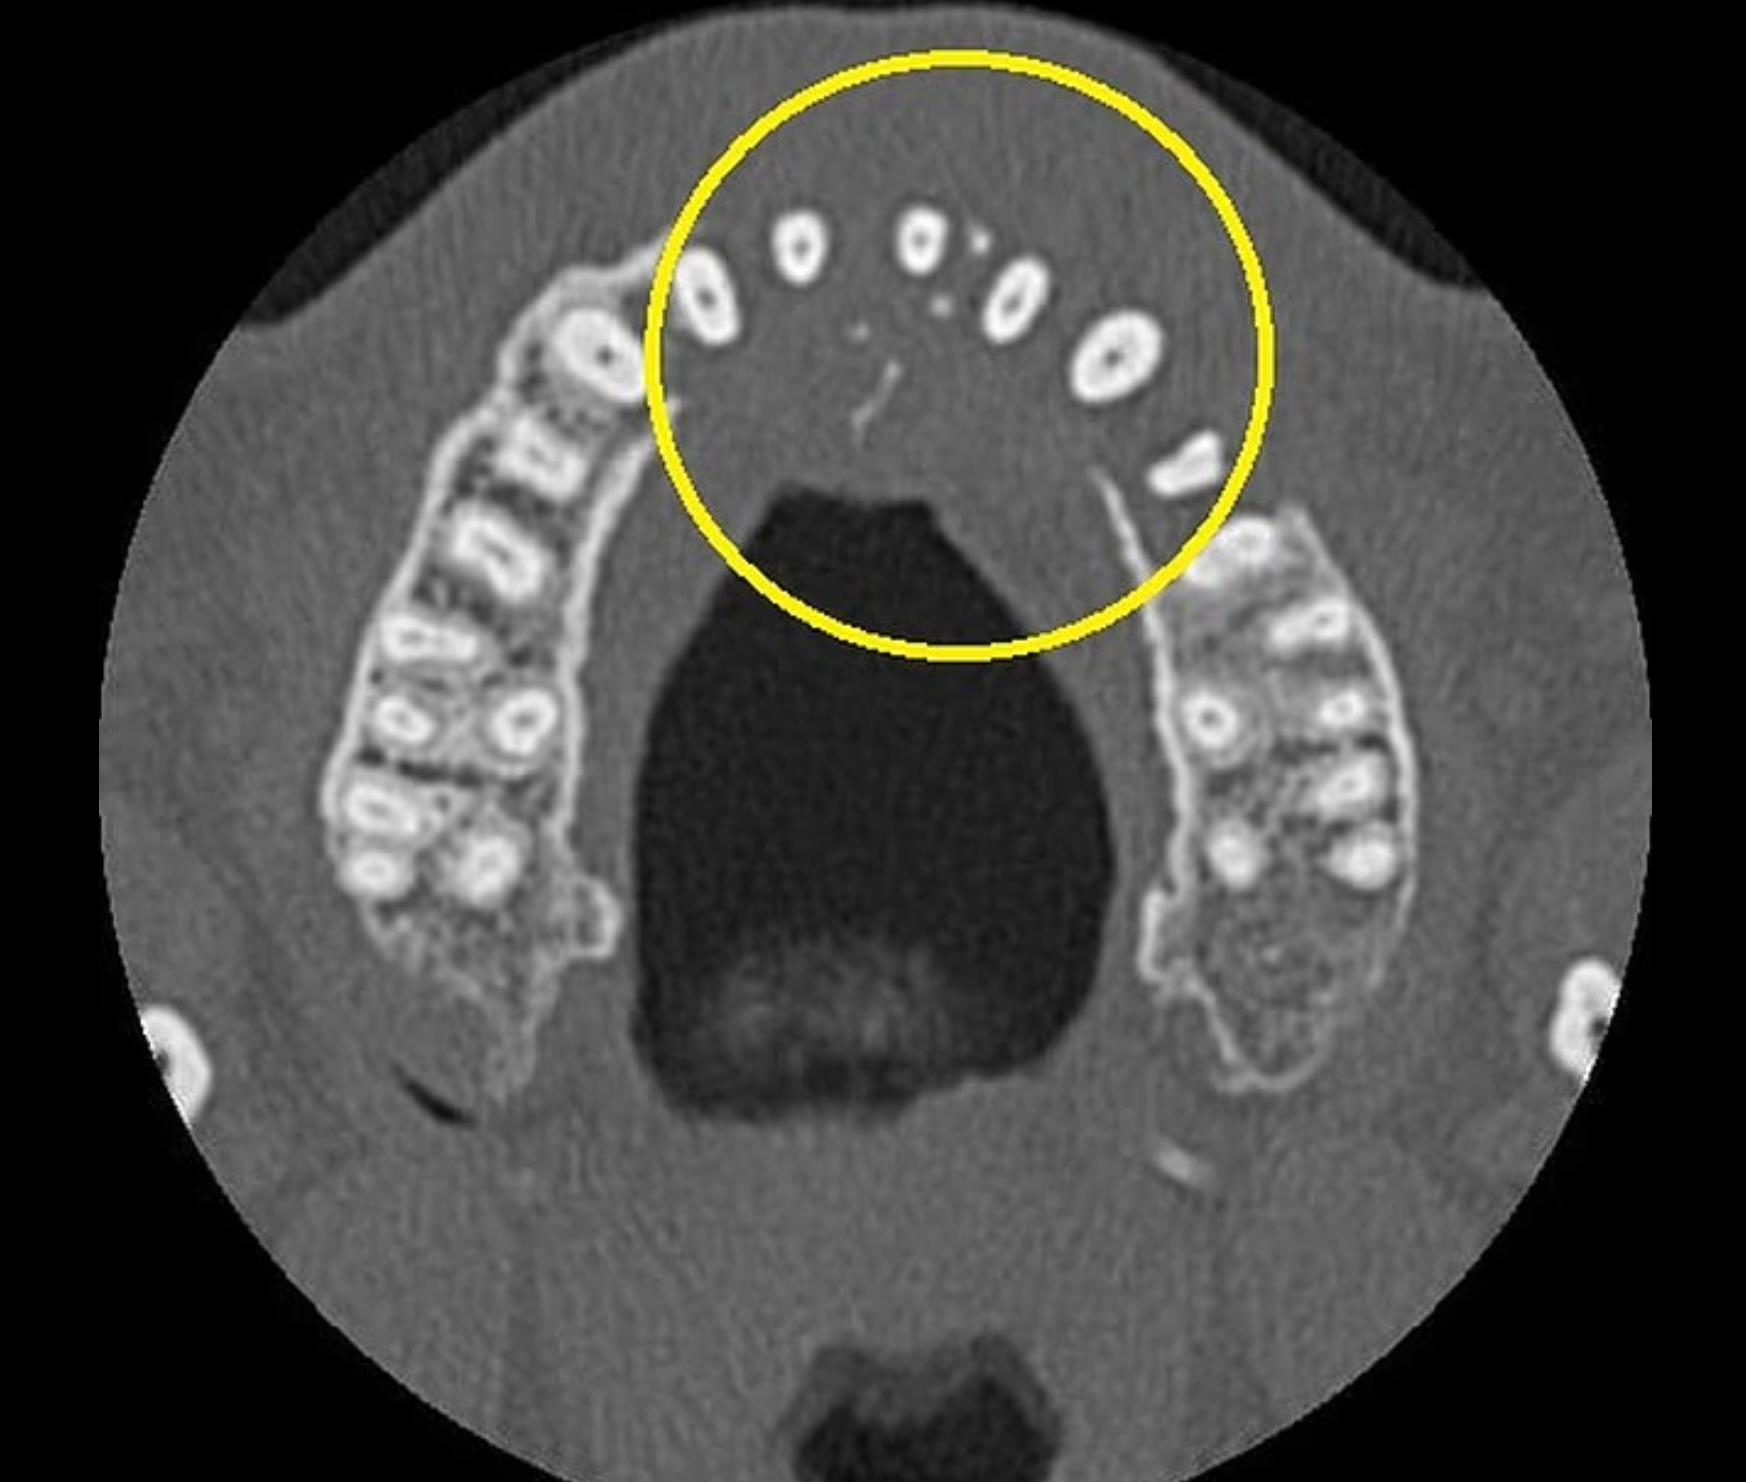

Edd形容擤鼻涕時會很痛,且注意到右側鼻孔旁邊有小硬塊。他到當地一間牙醫診所進行例行X光檢查,結果顯示其上顎左側沒有骨頭。CT掃描發現他的鼻竇腔內長有一個腫塊,並向鼻子下方擴散。

他回到英國後接受進一步檢查,最終證實他患有第二期瀰漫性大B細胞淋巴瘤(DLBCL),該是一種快速生長的非何杰金氏淋巴瘤,會影響白血球。X光片顯示,腫瘤已侵蝕他的上顎骨,癌細胞也開始擴散到頸部。